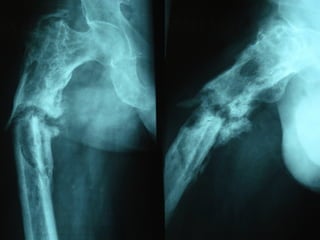

Paprosky

3-B (4)

Vanc. B - 3

21 mm

Subsidence

=

NO

LOOSENING

1999

1988

T 3 STEM